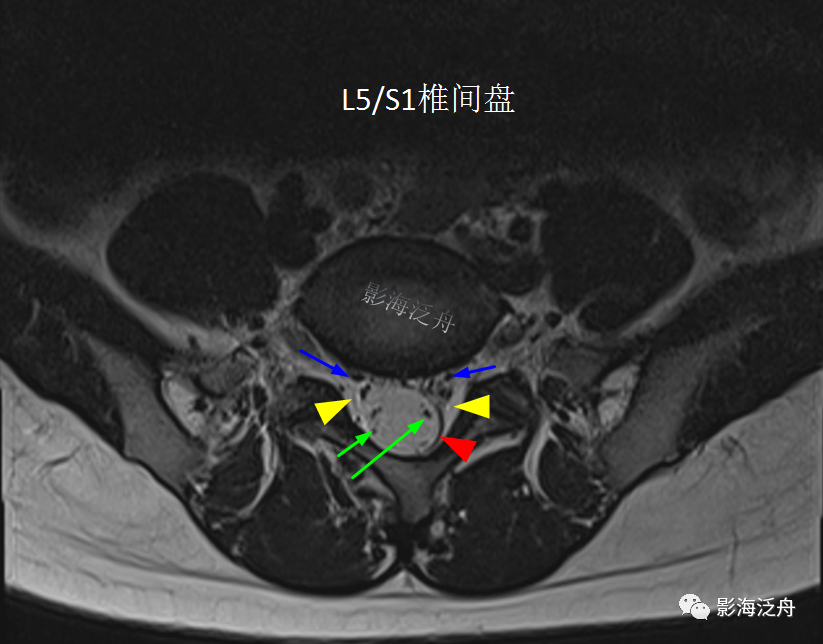

正常的腰骶部MR解剖:一般情况下,L5/S1层面是常规腰椎MR平扫横断位的最后一层,如上图所示,硬膜囊(红箭头)外只有很少量的脂肪(黄箭头)分布,马尾神经由硬膜囊内(绿箭)穿出并沿椎间孔区向外走行(蓝箭)。硬膜囊内的马尾神经均匀分散在硬膜囊边缘区。

开篇那个患者的L5/S1水平横断面图像:可见椎管内大部分空间被脂肪组织占据(黄箭头),硬膜囊显著受压呈“V字”形改变(红箭头),硬膜囊内的马尾神经聚拢在一起显示不清。